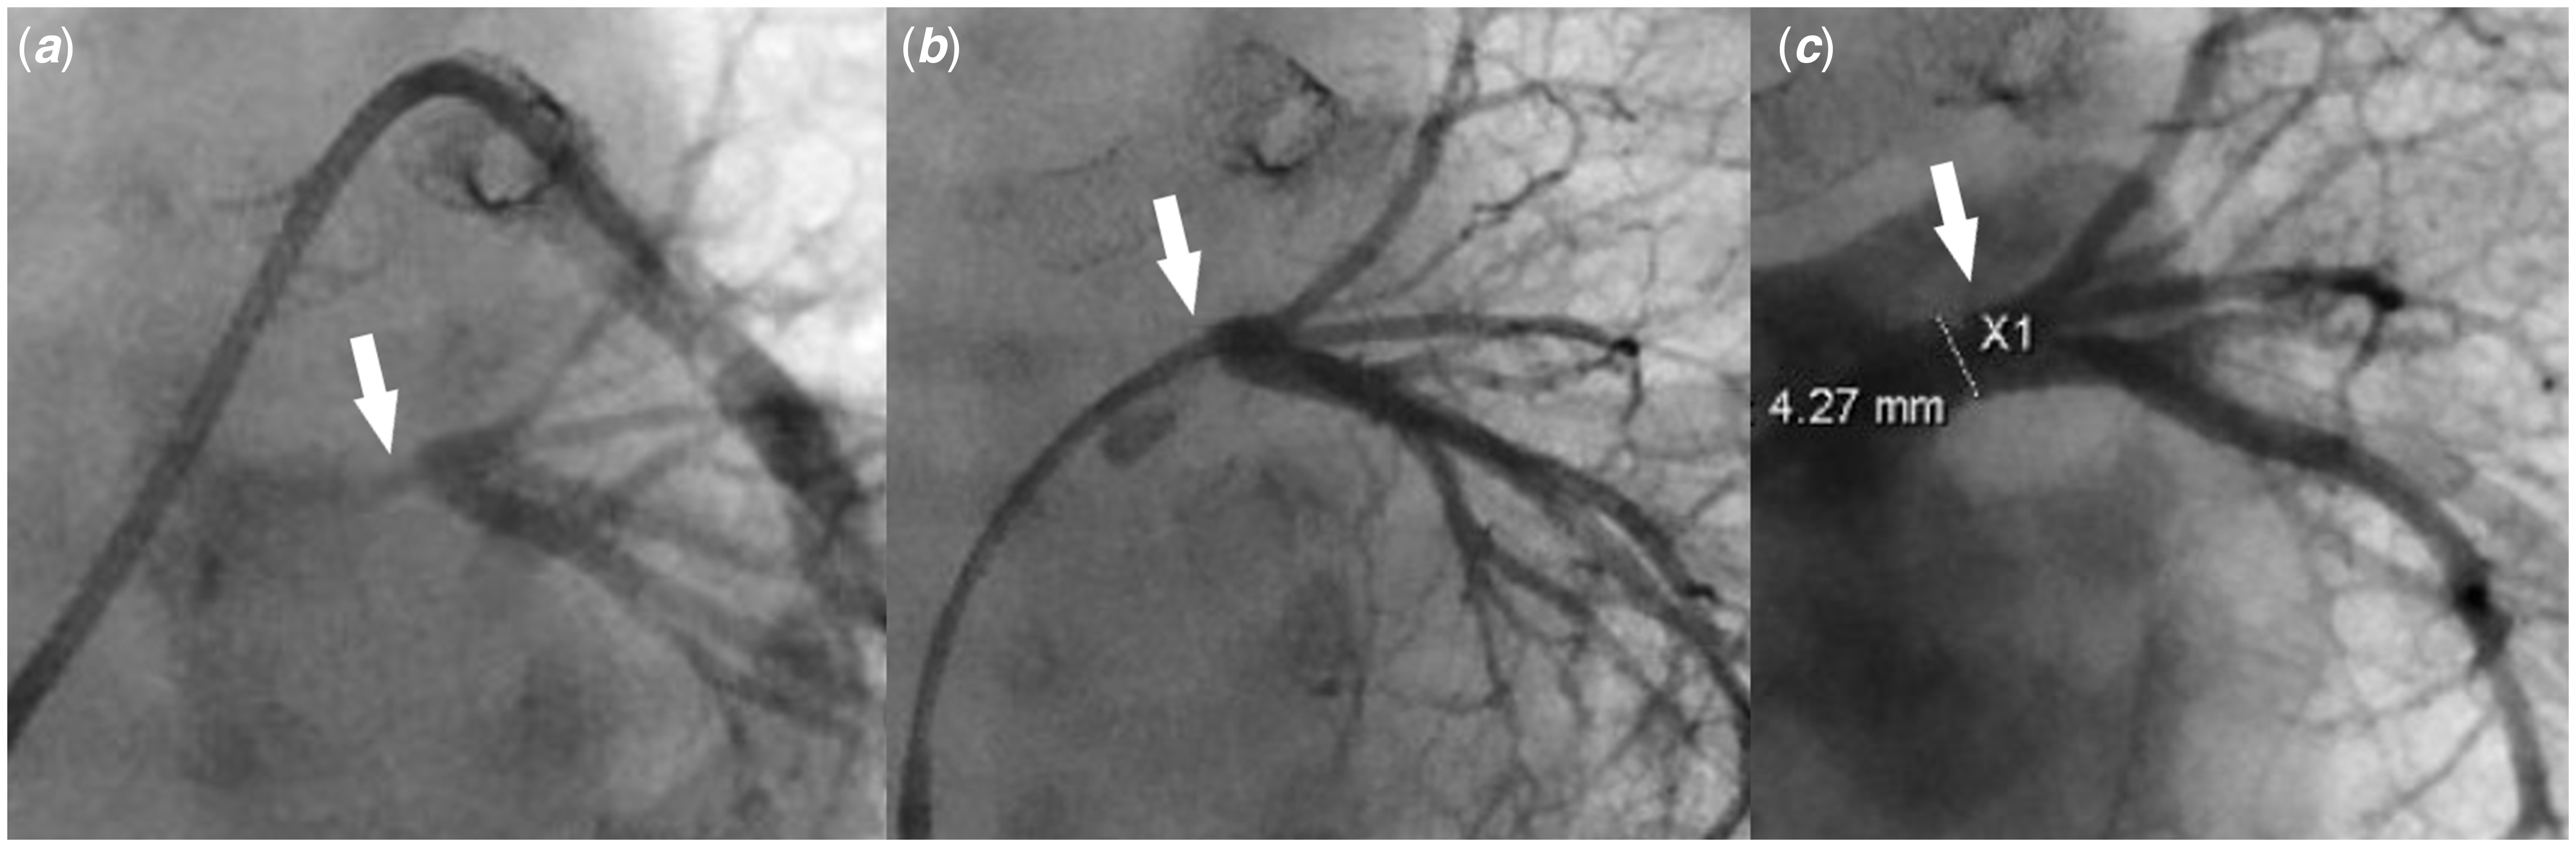

Figure 3. (a) Pulmonary artery wedge angiogram shows severe left common pulmonary vein ostial stenosis (white arrow). ( b) Left common pulmonary vein angiogram shows severe left common pulmonary vein stenosis (white arrow) with well-developed distal pulmonary vein branches. ( c) Left pulmonary vein angiogram post-stent placement shows a well-positioned stent (white arrow) inside the left common pulmonary vein with good expansion, resolution of the stenosis, and no evidence of vascular injury or jailing of the segmental left pulmonary veins.